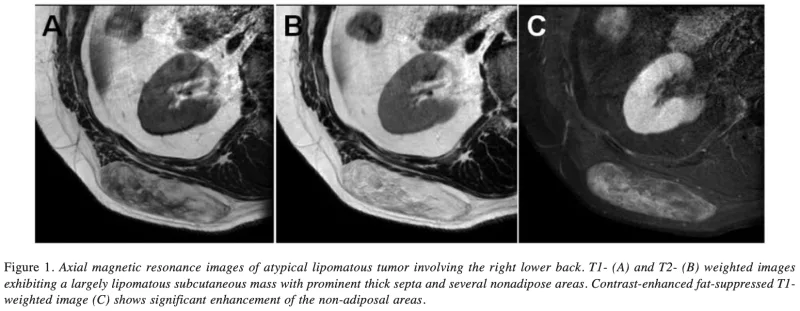

T1強調画像(A)では, 皮下脂肪と同じように白く写ります.

T2強調画像(B)と脂肪抑制下造影像(C)では, 腫瘍の大部分は黒く, 薄い隔壁が白く写ります.

MRI では, 僧帽筋の中に均一な脂肪成分を主体とした腫瘍を認め, 一部に淡い造影効果. 良性と悪性の中間である『異型脂肪腫様腫瘍』との鑑別が必要で, 摘出して病理検査を行う方針としました.

T1強調画像(A), T2強調画像(B)では, 脂肪成分の他に細胞が密に増殖しているのを反映して, 腫瘍の内部に黒い部分が広がっています.

造影MRI像(C)では, 細胞が密に増殖している部分が造影剤で白く写っており, 血管の増加を反映しています.

再発腫瘍のMRIを確認すると, 腫瘍の性状は前回より脂肪成分が減少し, 造影効果が増強. 『異型脂肪腫様腫瘍』の再発をより疑う所見に変化していました.